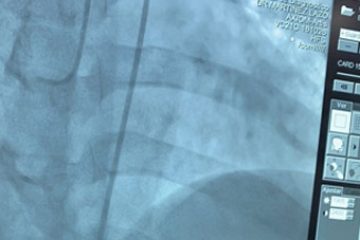

El latido cardíaco se interrumpe o para, llamado pausa sinusal o paro sinusal. Episodios de un ritmo cardíaco rápido. Ritmos cardíacos lentos alternados con ritmos cardíacos rápidos, llamado bradicardia-taquicardia o «sindrome taqui-bradi» Colocación de marcapaso Problema resuelto!